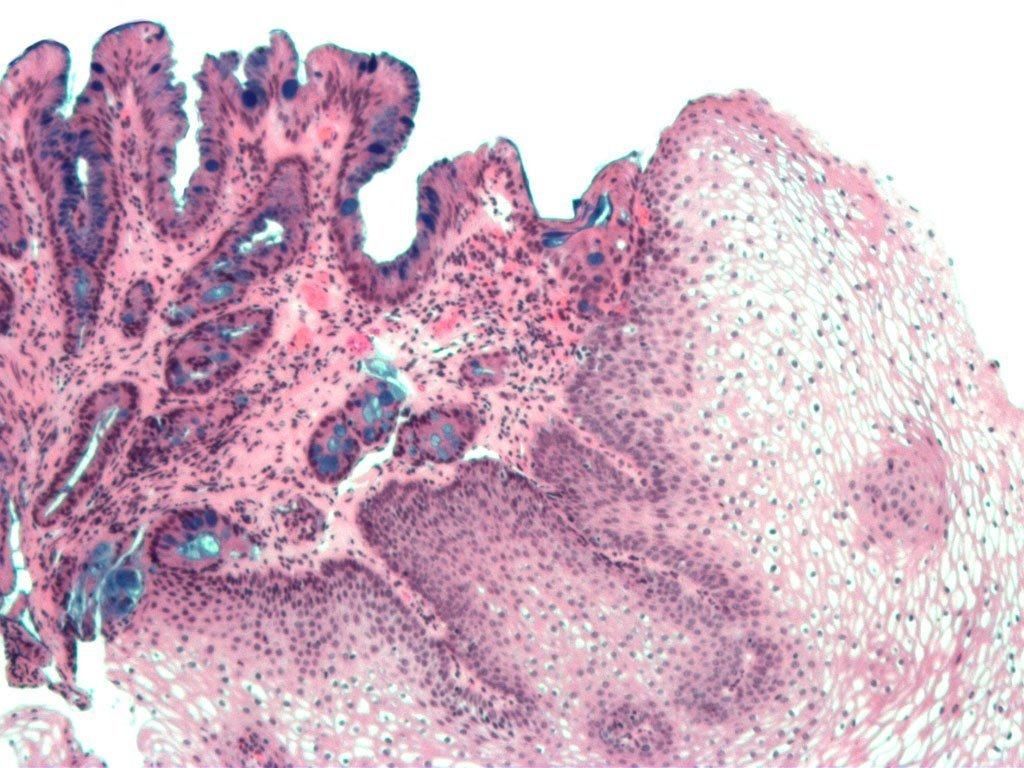

Dinding kerongkongan tersusun atas sel-sel rata dan pipih yang disebut sel skuamosa. Paparan asam secara terus-menerus dapat mengikis sel skuamosa dan mengubahnya menjadi sel kolumnar yang mirip dengan sel-sel pada dinding lambung.

Saat bentuk sel telah berubah itulah yang disebut sebagai Barrett’s esophagus. Kondisi ini berkaitan dengan meningkatnya risiko kanker esofagus.

Jaringan kerongkongan yang normal akan tampak pucat dan mengilap. Sementara itu, jaringan kerongkongan yang mengalami kerusakan tampak kemerahan dengan tekstur seperti beludru.

Dokter juga dapat melakukan pengambilan sampel jaringan (biopsi) pada pemeriksaan yang sama. Hasil biopsi akan menunjukkan tingkat keparahan penyakit dan apakah ada tanda-tanda jaringan kanker.